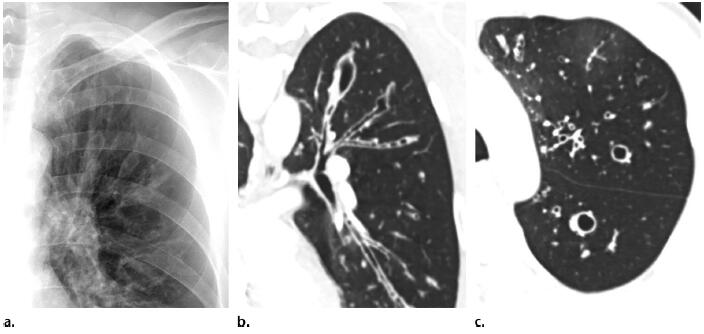

支气管扩张的影像特征有哪些?

支气管扩张是由于支气管及其周围肺组织慢性化脓性炎症和纤维化,使支气管壁的肌肉和弹性组织破坏,导致

支气管扩张是亚段支气管永久性的异常扩张,其病因可分为先天性和后天性两种。一种用于后期严重的支气管扩张

肺部支气管扩张是一种医学病症名,它是指由于支气管及其周围组织的慢性炎症和气道阻塞,导致支气管的组织